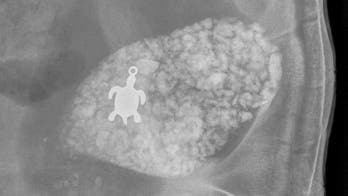

November 30, 2015 Veterinarian's X-ray reveals sick tortoise in south Florida had swallowed small turtle pendant The source of a sick tortoise's discomfort became clear after a south Florida veterinarian took an X-ray: The animal had swallowed a turtle pendant.